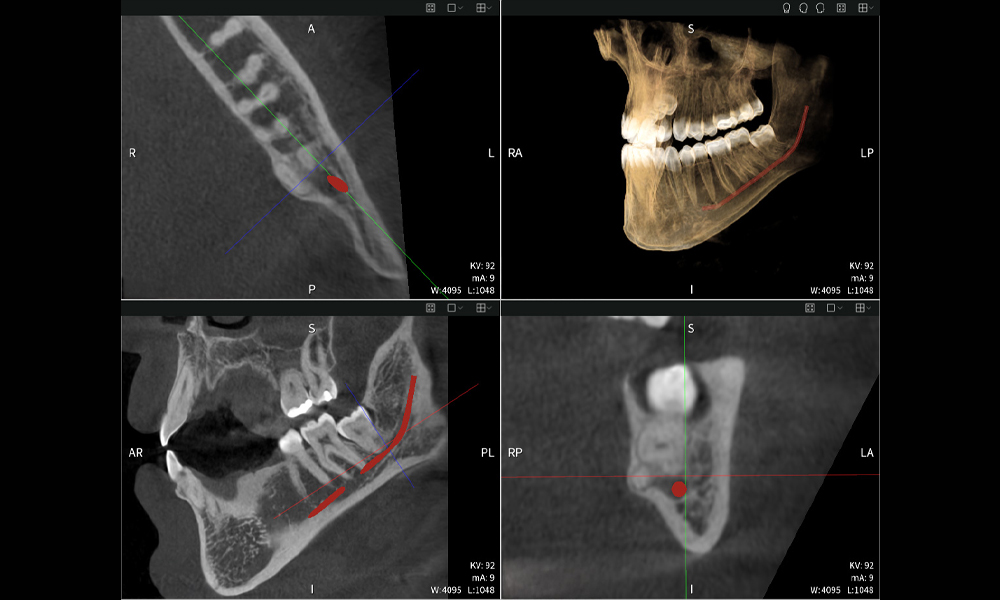

Nachstehend finden Sie einen Fall von Dr. med. dent. Oliver A. Centrella, in dem die CBCT-Aufnahmen mit Seethrough Max entscheidende Informationen zur komplexen Anatomie sowie zur kritischen Beziehung zwischen den Weisheitszähnen und dem Nervus alveolaris inferior lieferten. Bei diesem Fall besteht eine Indikation zur chirurgischen Entfernung der Weisheitszähne.

Abbildung a: Bildgebungsergebnisse von Seethrough Max vor einem schwarzen Hintergrund.

• Oben links: Axiale Schnittansicht des linken Unterkiefers (Region 38) mit Darstellung des Nervus alveolaris inferior (rot) in unmittelbarer Nähe zu den Wurzeln des Zahns 38.

• Oben rechts: 3D-Rekonstruktion des gesamten Unterkiefers zur Orientierung. Der rot markierte Nervus alveolaris inferior verdeutlicht seine Lage im Kieferknochen.

• Unten links: Sagittale Ansicht des Unterkiefers (Region 38), die die enge räumliche Beziehung zwischen den Wurzeln und dem Nervenkanal verdeutlicht.

• Unten rechts: Koronale Ansicht des Unterkiefers (Region 38) entscheidend für die Beurteilung der räumlichen Lage der Wurzeln zum Nerven.